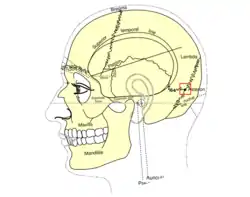

Side view of head, showing surface relations of bones. (Asterion visible at center right.) | |

In human anatomy, the asterion is a visible (craniometric) point on the exposed skull. It is just posterior to the ear. It is the point where three cranial sutures meet:

It is also the point where three cranial bones meet:

- the parietal bone.

- the occipital bone.

- the mastoid portion of the temporal bone.

In the adult, it lies 4 cm behind and 12 mm above the center of the entrance to the ear canal. Its relation to other anatomical structures is fairly variable.[2]